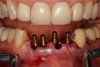

Fig 39. Surgical guide in place.

Figure 39

Fig 40. 3 x 13-mm implants.

Figure 40

The next case follows the digital protocol for fully guided surgery and prosthetics. A CBCT radiograph, digital impression, and digital photography were the cornerstones to the success of this case. The 3D data set was electronically delivered to the dental laboratory. The data were merged and the process to develop the plan was initiated. The use of CBCT was essential in this case, particularly due to minimal space for placement of individual implants and single-unit crowns. The patient's chief concern was that she wanted to have single-unit crowns instead of fixed crown-and-bridge restorations because she was worried that she would someday find herself in an assisted-living facility; if that were to happen, she wondered, who would help floss under her bridge work? Her decision was to have single implants with individual crowns. CBCT technology is much more accurate in evaluating space maintenance and management.10 Periapicals in the past were rather close for calculating spacing; however, the CBCT identifies the buccal-lingual dimensions as well as the mesial-distal measurements. On review of the completed proposals for implant placement and provisionals, it was determined that there was sufficient spacing for implant placement to allow appropriate emergence profiles for the provisionals and then eventually the final single-unit cemented crowns. The proposal was accepted, and a 3D-printed surgical stent was fabricated, along with the PMMA provisionals (Figure 29 through Figure 35).

On the day of surgery, the plan was to extract teeth Nos. 21, 23, 24, 25, and 26, place 3.0 x 13-mm implants in the anterior region due to limited spacing, and place a 4.1 x 10-mm implant in the No. 21 extraction site. Before the extractions were performed, the No. 23 pontic was sectioned from the existing 2-unit cantilevered bridge utilizing ceramic and metal high speed rotary cutting burs ZR 6881 and H34L (Komet-USA), respectively. After removal of the pontic and extractions, the surgical guide was verified to be seating positively (Figure 36 through Figure 38). Surgical guide protocol was followed, and all implants were successfully placed and torqued to a value of greater than 35 Ncm (Figure 39 and Figure 40). All implants were placed without flapping, with the exception of No. 23. The flap was elevated to reposition lingual keratinized tissue facially for enhanced esthetic tissue profile. The implants were then prepared with a high-speed carbide bur (Komet-USA) with copious amounts of water (Figure 41 and Figure 42). The one-piece 3.0-mm diameter implant served the needs of the patient's spacing requirements. Inter-occlusal space requirements and path of draw were verified. The PMMA provisionals were air abraded and relined with crown-and-bridge material (Figure 43 through Figure 45).